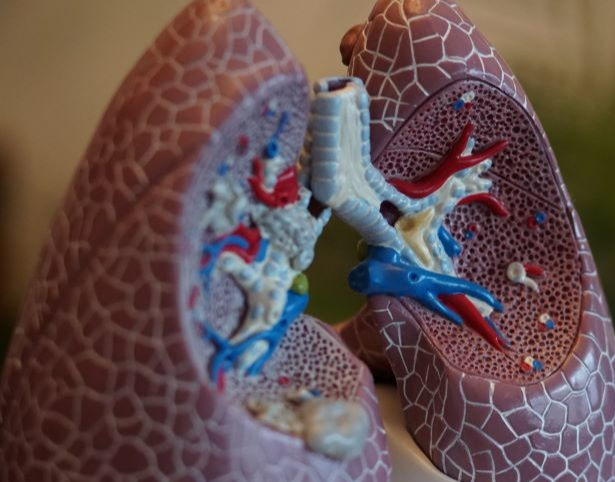

폐암은 국내 암 사망률 1위로, 과거에는 흡연이 폐암의 주요 원인이었지만 최근에는 비흡연자의 폐암 발병이 크게 증가하고 있습니다. 폐암은 오랜 기간 암 사망률 1위를 차지하고 있지만, 의학의 발전으로 생존율이 높아지고 있습니다. 그러나 초기 단계에서 올바르게 관리하는 것이 중요합니다. 폐암의 초기 징후가 무엇인지, 폐암에 좋은 음식은 무엇인지 알아두는 것이 좋습니다.